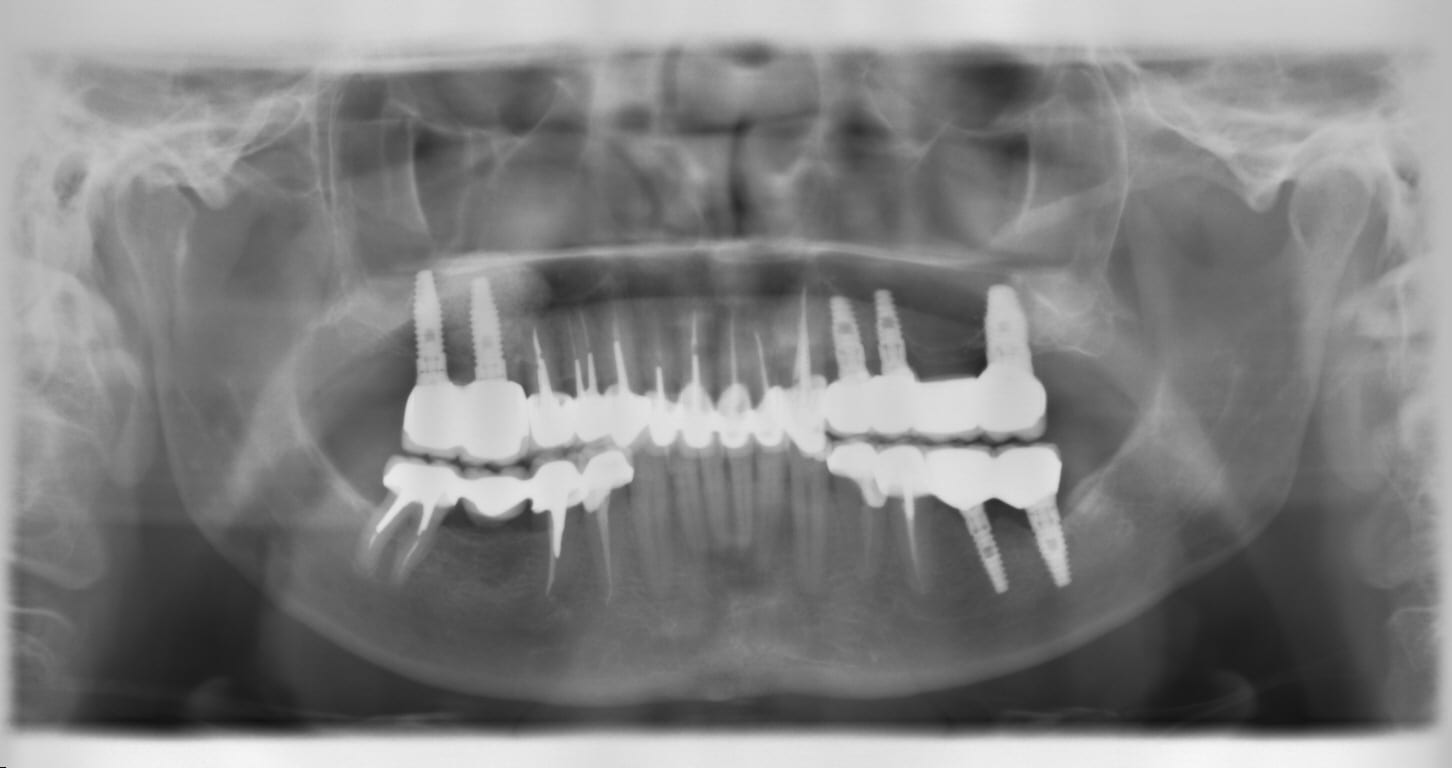

CASE 30

3 implants with 4-unit bridge upper left, 2 individual implants on upper right and lower left